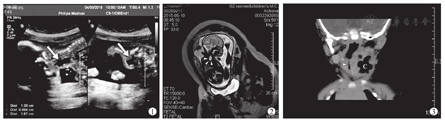

产前诊断组男2例,女6例,产检B型超声首次检出平均孕周为(27.00±6.76)周。首次B型超声检查提示7例为左侧颈部肿物(图1),1例为双侧颈部包块;8例均为壁厚、单房的低回声包块。胎儿MR检查均提示与甲状腺关系密切,1例双侧颈部包块提示气管有推移,7例左侧颈部包块均无气管移位(图2)。生后临床表现为左侧颈部肿物7例,双侧1例,发热2例,气道梗阻1例,声音嘶哑1例。生后MRI发现特征性气液平面4例,食道造影检查阳性3例。

产后诊断组男6例,女2例,首次疑诊时间为生后(10.14±8.84) d。生后临床表现为左侧颈部肿物8例(图3),发热3例,气道梗阻7例,声音嘶哑2例。生后MRI发现特征性气液平面7例,食道造影检查阳性1例。